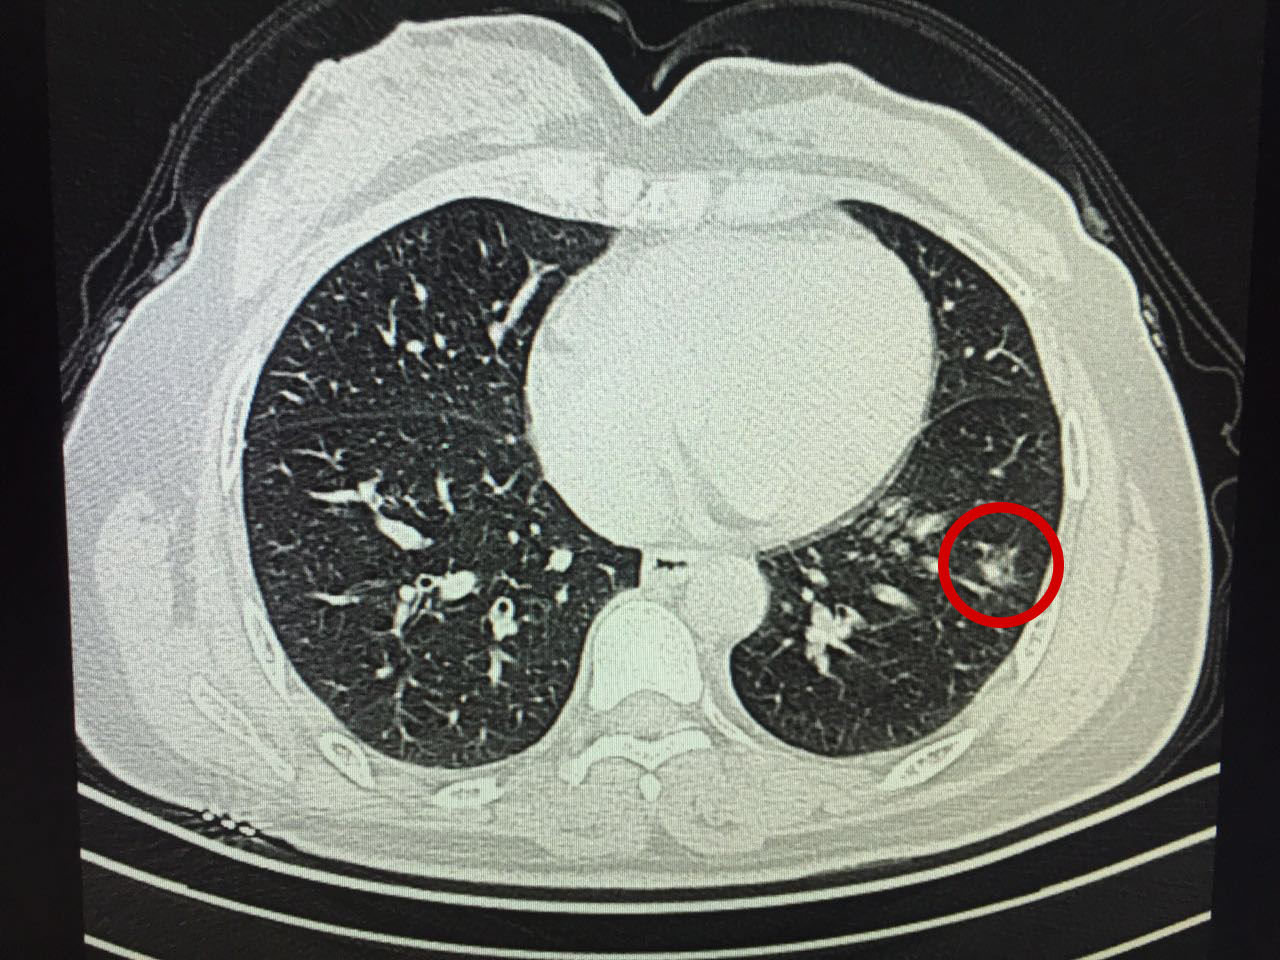

“情况还不错。”王剑飞原本严肃的脸上此刻挂上了淡淡的微笑,“你看,虽然大小几乎没变,但是变淡了,这是好现象。”他指点着结节部位,又调出之前的片子做对比。

一个月后,吴女士再次来到肺结节中心进行第二次复查,而结果简直令她惊喜——结节已缩小至6mm,几乎都看不清了!